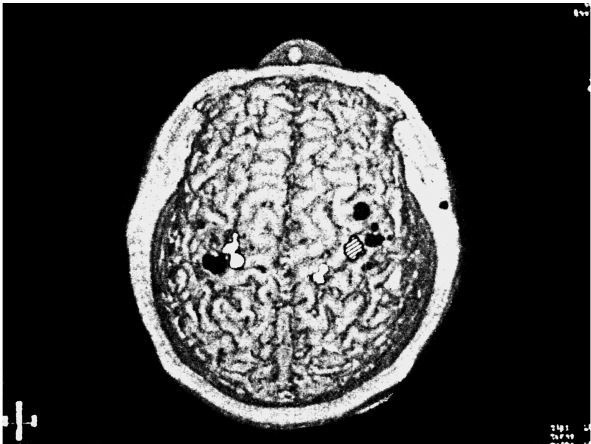

С помощью МЭГ всего за два часа можно составить карту мозга любого человека, изъявившего желание сесть под магнит. Неудивительно, что полученная карта очень похожа на гомункулуса Пенфилда (индивидуальные вариации в общем расположении карты крайне малы). Однако, обследовав четырех пациентов с ампутацией верхних конечностей, мы обнаружили, что карты сильно изменились — точь-в-точь как мы и предсказывали. Например, взглянув на рисунок 2.3, вы увидите, что зона кисти в правом полушарии (заштрихована) захвачена сенсорными сигналами от лица (показаны белым) и верхней части руки (показаны серым). Эти наблюдения, которые мне удалось сделать в сотрудничестве с аспирантом Тони Янгом и неврологами Крисом Галленом и Флойдом Блумом, стали первой в истории непосредственной демонстрацией крупномасштабных изменений в организации мозга у взрослых людей.

Иллюстрация к книге — Фантомы мозга [i_006.jpg]

Рис. 2.3

Магнитоэнцефалограмма, наложенная на изображение, полученное методом магнитного резонанса (вид сверху). Правая рука пациента ампутирована ниже локтя. В правом полушарии наблюдается нормальная активация областей коры, связанных с кистью (заштрихована), лицом (показана черным) и верхней части руки (показана белым). В левом полушарии активность в области, соответствующей ампутированной правой кисти, отсутствует. Активность, вызванная прикосновениями к лицу и верхней части руки, теперь «распространяется» и на эту зону.